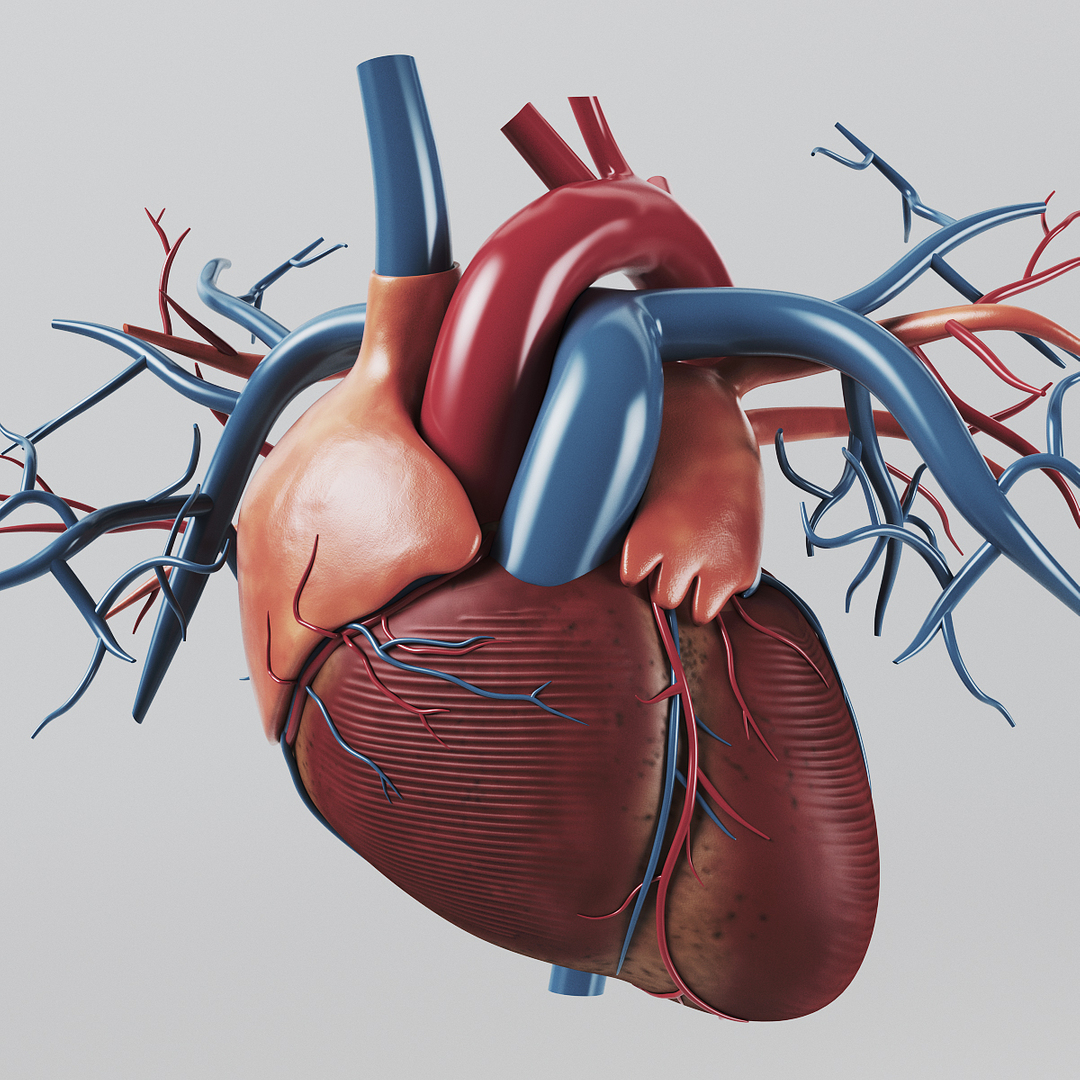

Human Heart Anatomy 1 3D model | CGTrader  How to draw realistic human heart||3d human heart sketch

Human Heart Anatomy 1 3D model | CGTrader  human heart anatomy 3d max

human heart anatomy 3d max  Heart Anatomy Human Heart Images Hd 3D - Dreaming Arcadia